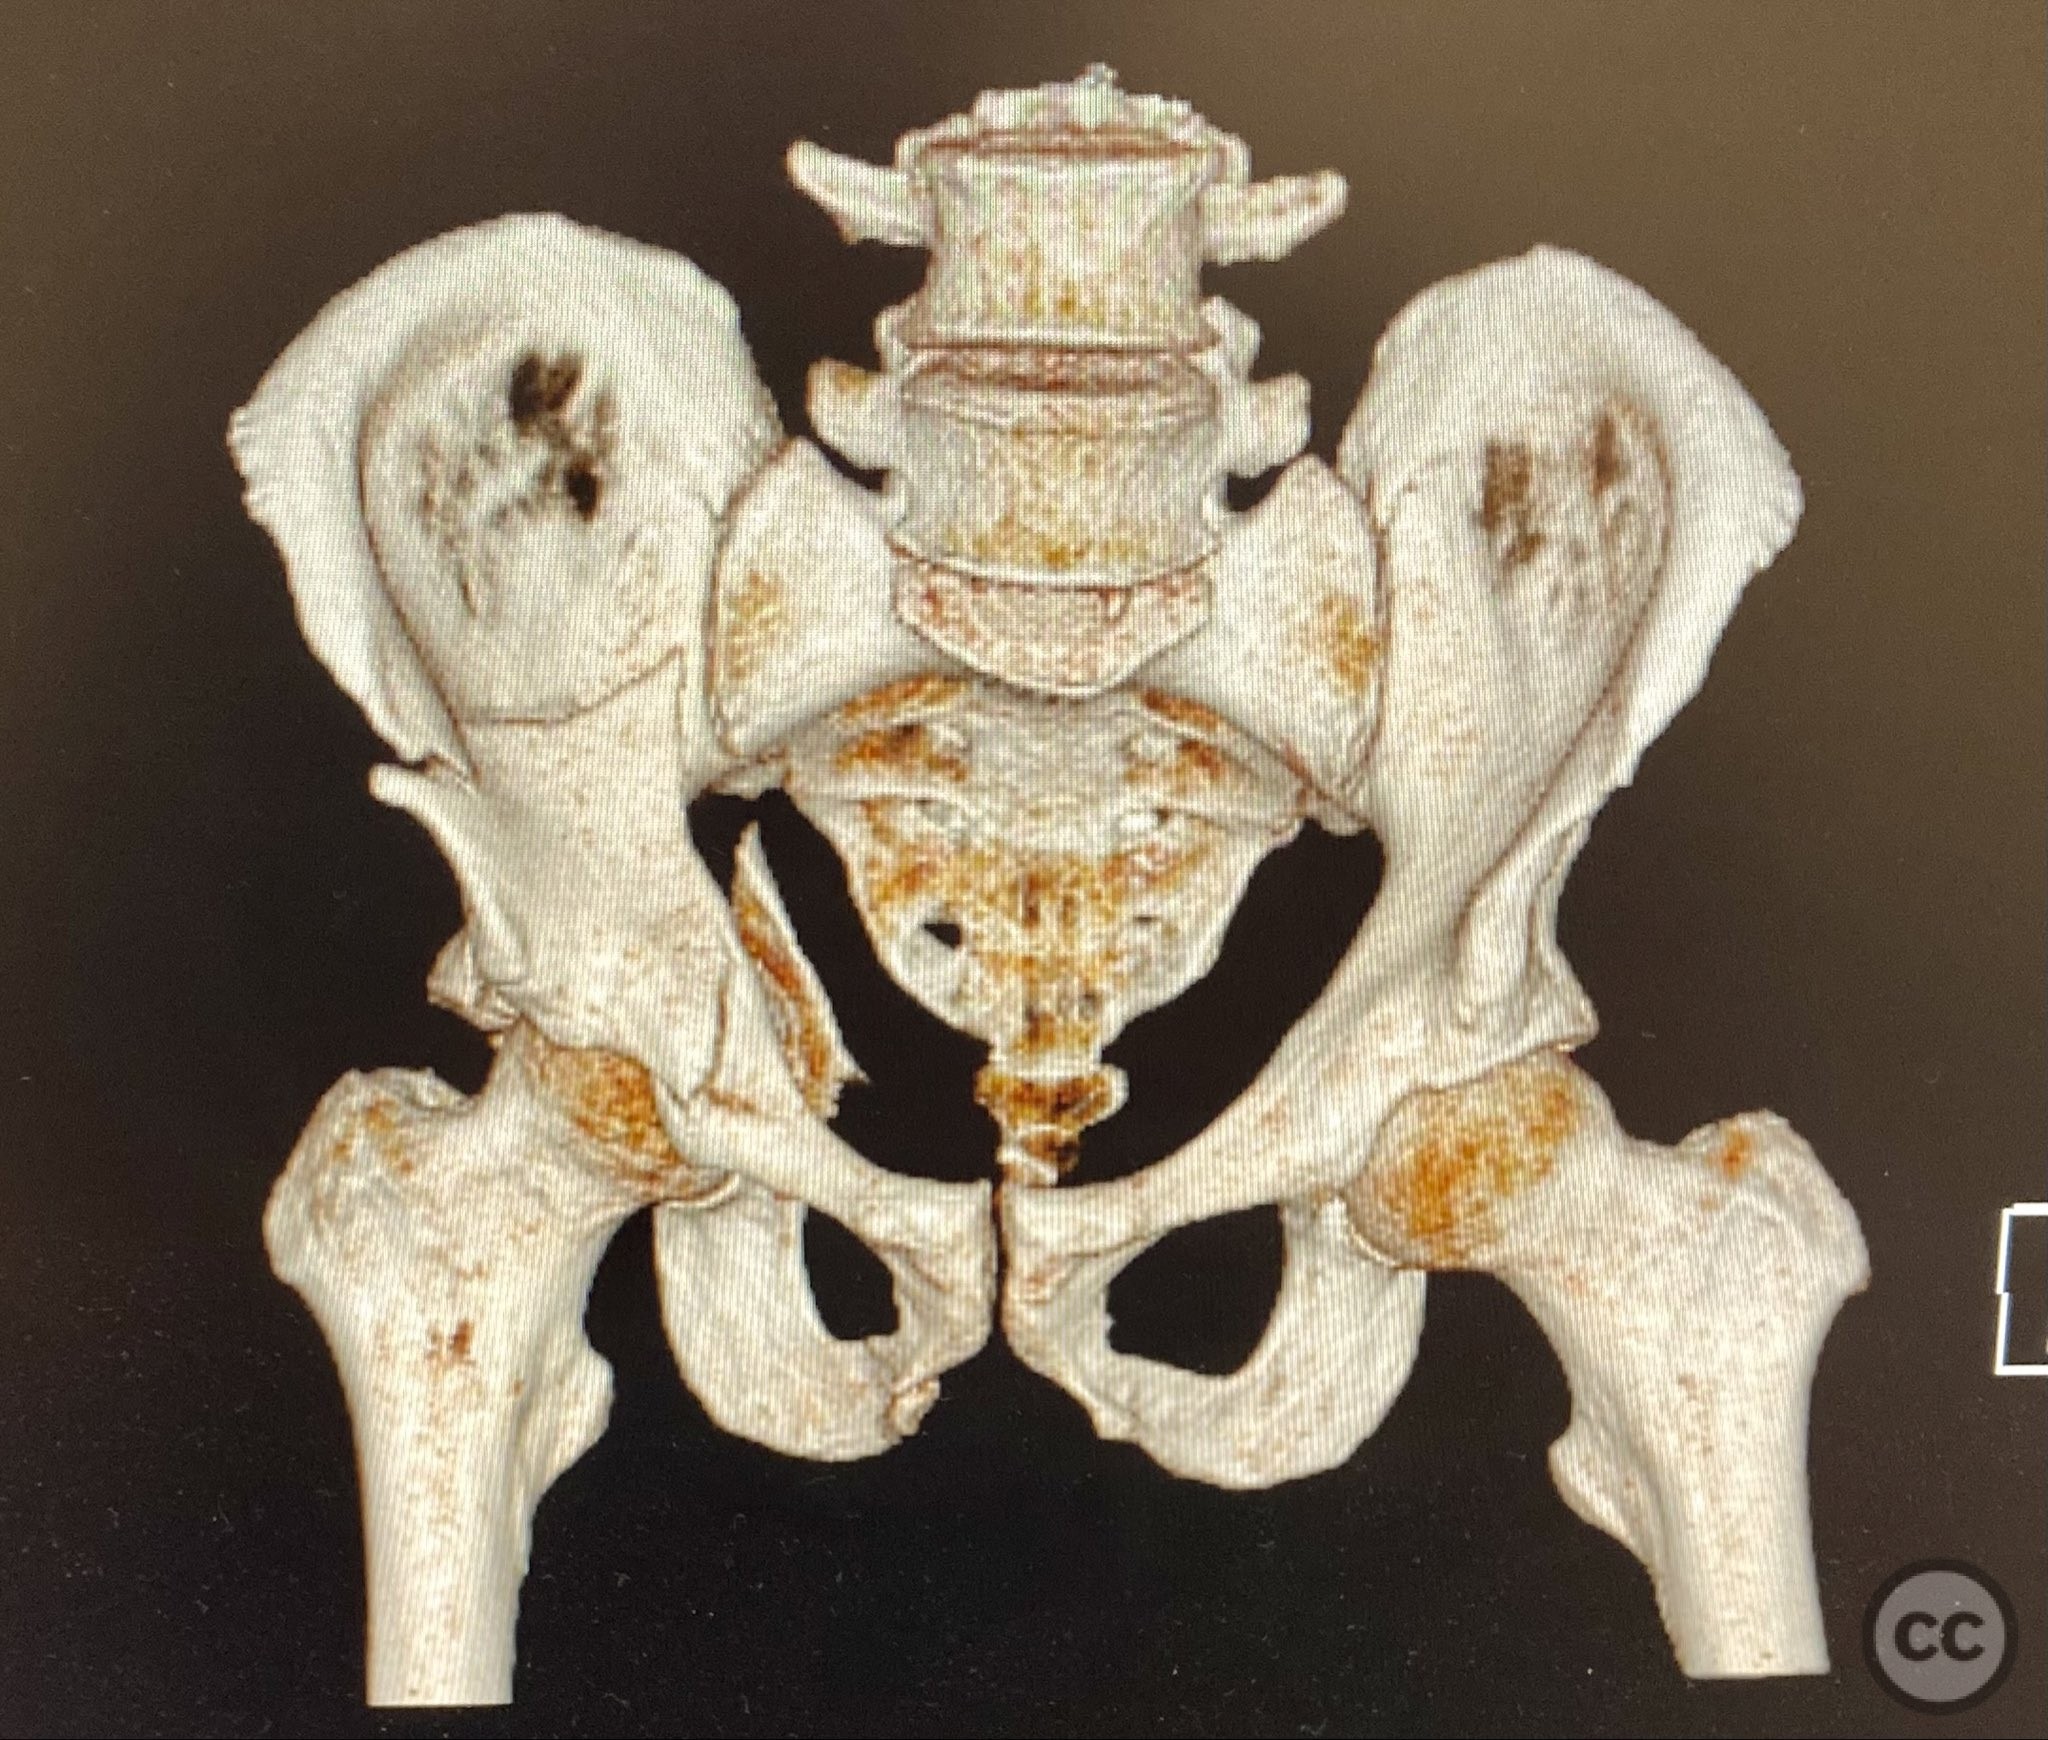

Clinical and radiological findings:  A patient presented with a combined anterior column and posterior hemi-transverse (AC/PHTr) acetabular fracture. Plain radiographs demonstrated multiple displaced fragments involving the acetabular dome and femoral head region, with clear disruption of the anterior column and posterior transverse components. Advanced imaging, including axial and coronal CT, provided detailed visualization of cortical surface displacement, fragment orientation, and associated soft tissue status. The edge of the intact dome and femoral head injuries were identified, as well as a residual defect at the edge of the dome following reduction. AO/OTA classification: 62B2 (anterior column with posterior hemitransverse).

Surface renderings from preoperative imaging facilitated intraoperative correlation between radiographic and fluoroscopic views, aiding in precise interpretation of fragment orientation during reduction. The use of focal plates allowed for maintenance of provisional reductions with bone holding clamps during definitive fixation. Restoration of radiographic lines was confirmed on intraoperative AP fluoroscopy, while postoperative axial CT demonstrated successful central dome repair with a residual edge crush defect at the dome margin.